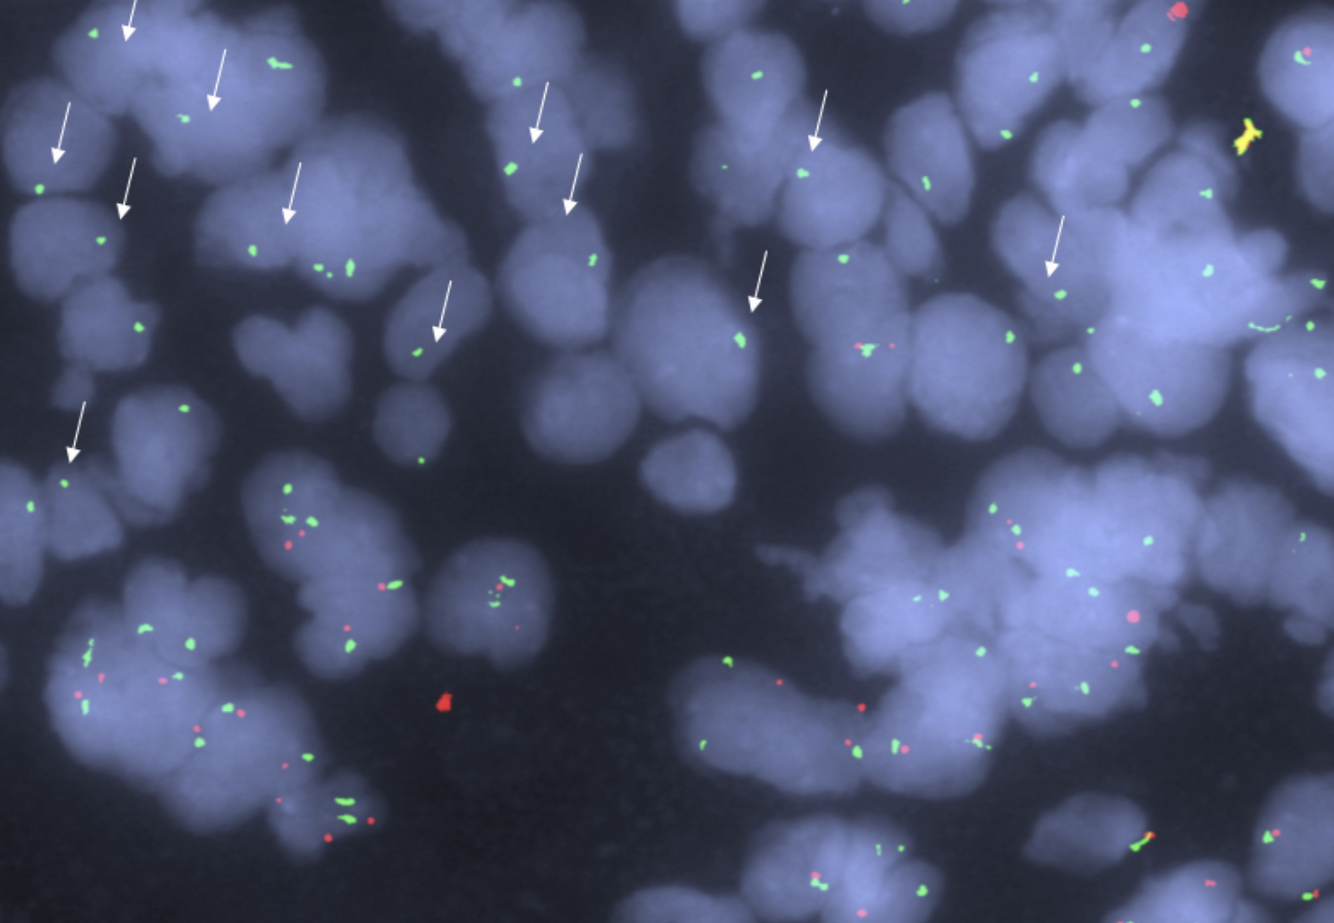

Approach to FISH interpretation in lymphomas

Lymphomas often have many overlapping cells, making FISH interpretation difficult.

Take your time, find as best of monolayers as you can, check 10-15 fields before deciding if something is truly negative.